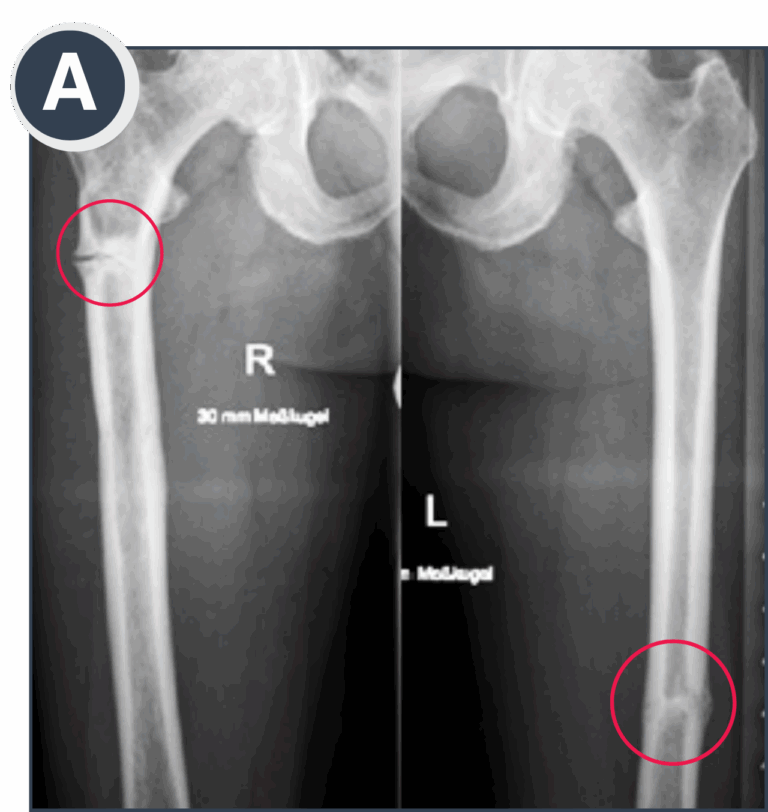

A: Bilateral femoral pseudo-fractures, progressed to almost complete fractures. Symptomatic and painful on the right side, while the left side was asymptomatic and a coincidental finding following thorough skeletal assessment.

B: Course of fracture healing at 6 months after intramedullary rodding on the more critical right side and initiation of enzyme replacement therapy.